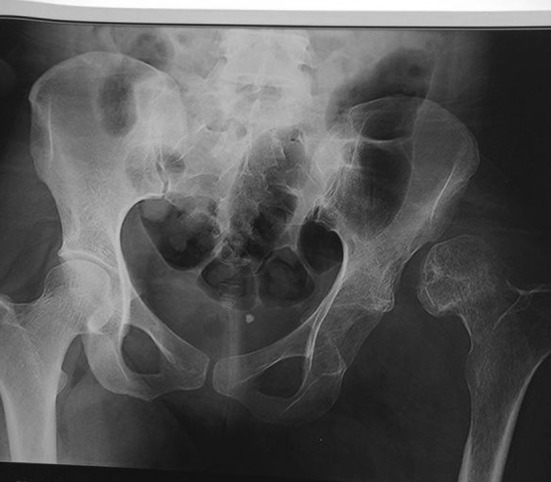

Preoperative X-ray of pelvis with neglected hip dislocation with false hip joint

We saw this patient 2 years after the initial injury complaining of hip pain. She was walking with an antalgic gait and had a decreased range of motion of her hip. The limb was in fixed adduction and internal rotation. She had a leg length discrepancy due to shortening of 6 cm. Her hip movements were restricted and painful. Radiographs confirmed a persistent dislocation of the hip, with a false acetabulum in the left supra-acetabular region.